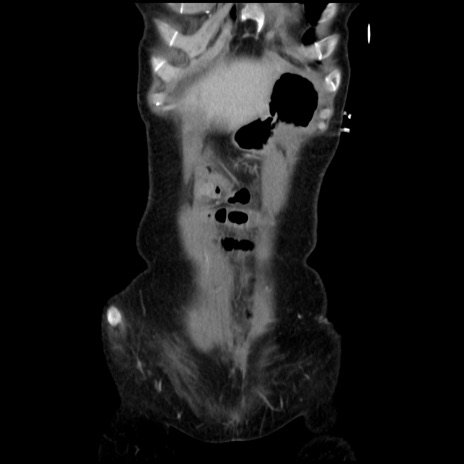

症例32(冠状断像)

【症例】40歳代 女性

【主訴】上腹部痛、嘔気・嘔吐

【現病歴】約9時間前頃から急に上腹部痛、嘔気、嘔吐が出現。改善しないため救急要請。

【既往歴】子宮頚癌(広汎子宮全摘術、放射線療法)、腸閉塞

【身体所見】腹部:平坦、軟、腸雑音亢進、上腹部を中心に腹部全体に圧痛あり。

【データ】WBC 8400、CRP 0.03